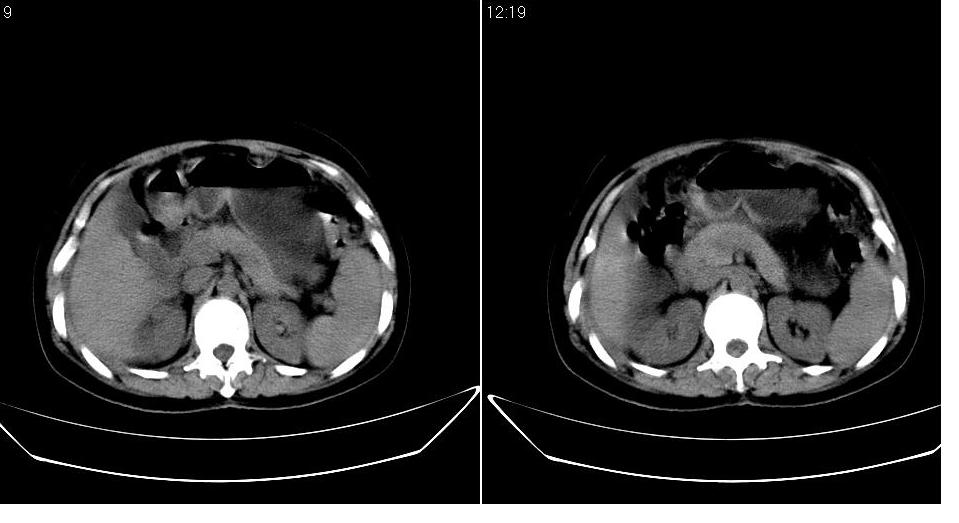

以下是引用zbp537在2009-1-19 14:09:00的发言:[br]从这个平扫图像上看,只能考虑:1、胸腹水。2、脾脏包膜下弧形高密度影,疑出血,建议复查。[br]既然腹水中有恶性细胞,建议行腹部ct增强扫描及胸部扫描。

以下是引用随光逐影在2009-1-19 15:47:00的发言:[br]1)不排除胃癌可能;建议行胃镜检查。2)腹水。3)右侧胸腔积液。

以下是引用jiangjing在2009-1-19 18:21:00的发言:[br]1 网膜污垢征---肿瘤网膜转移.2)腹水。3)右侧胸腔积液